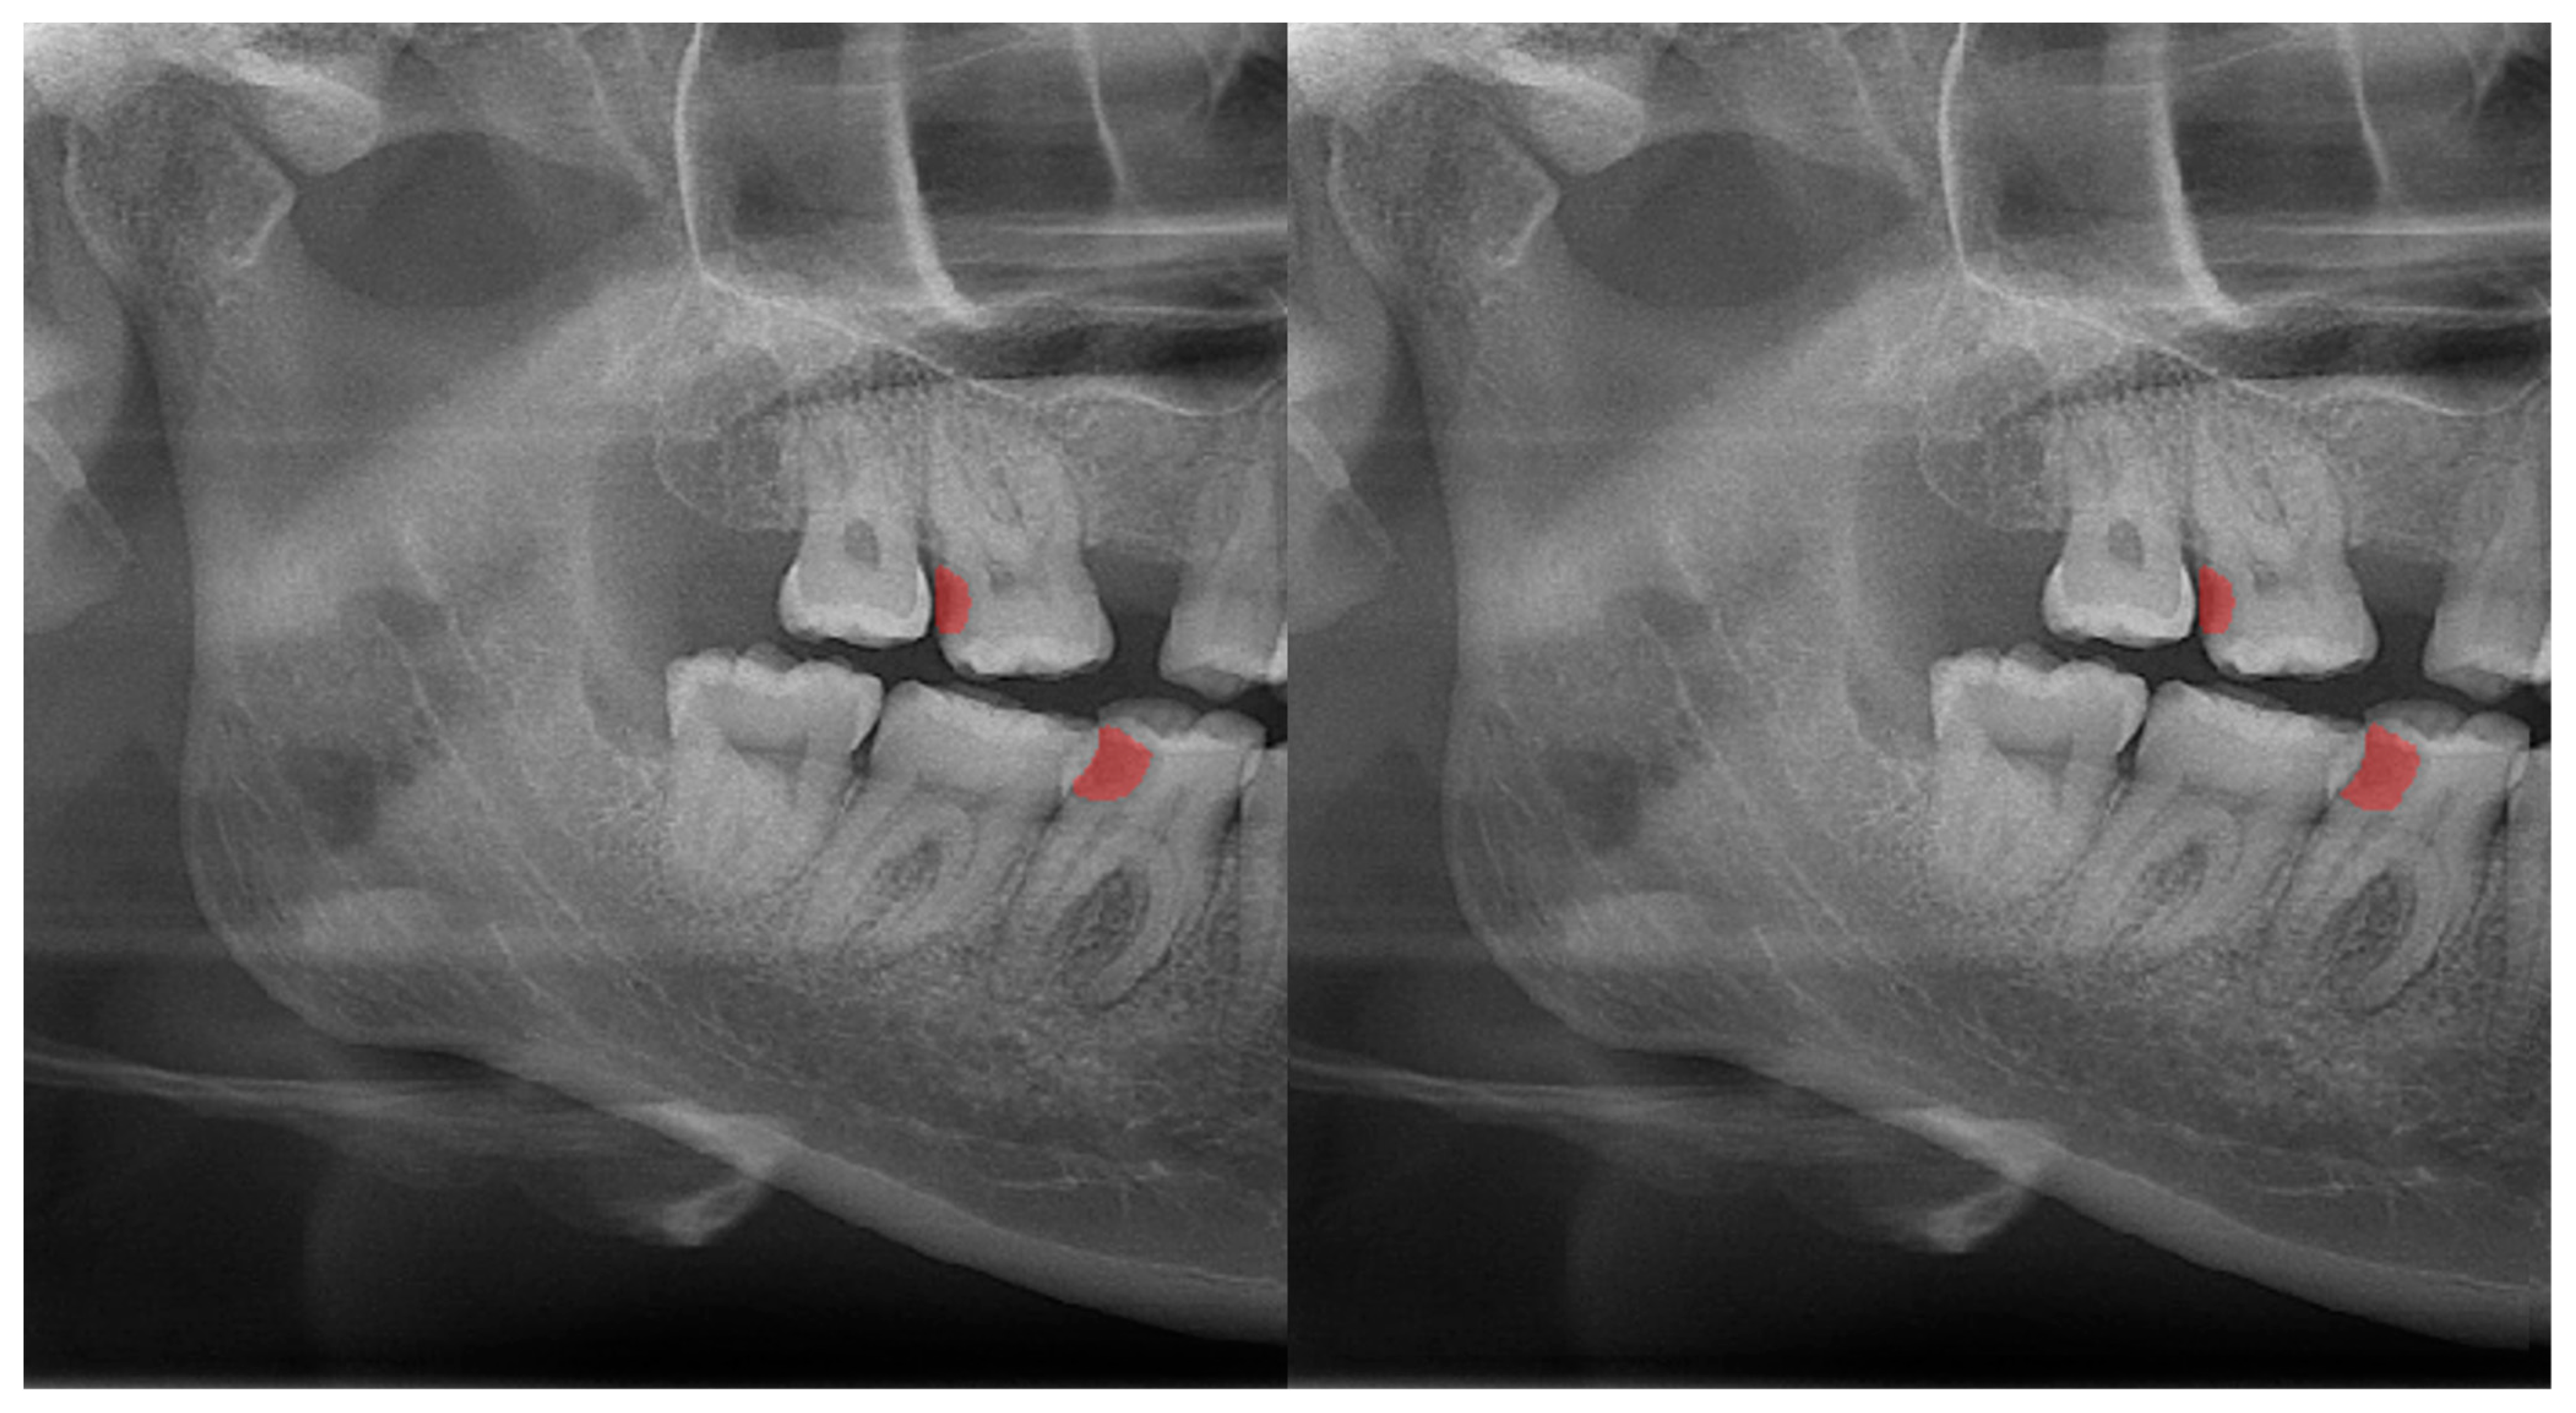

Figure 3.

Automatic segmentation of the carious lesions at the upper-left second molar and lower-right first molar. Manual segmentation (left) as well as automatic segmentation (right) can be seen above.